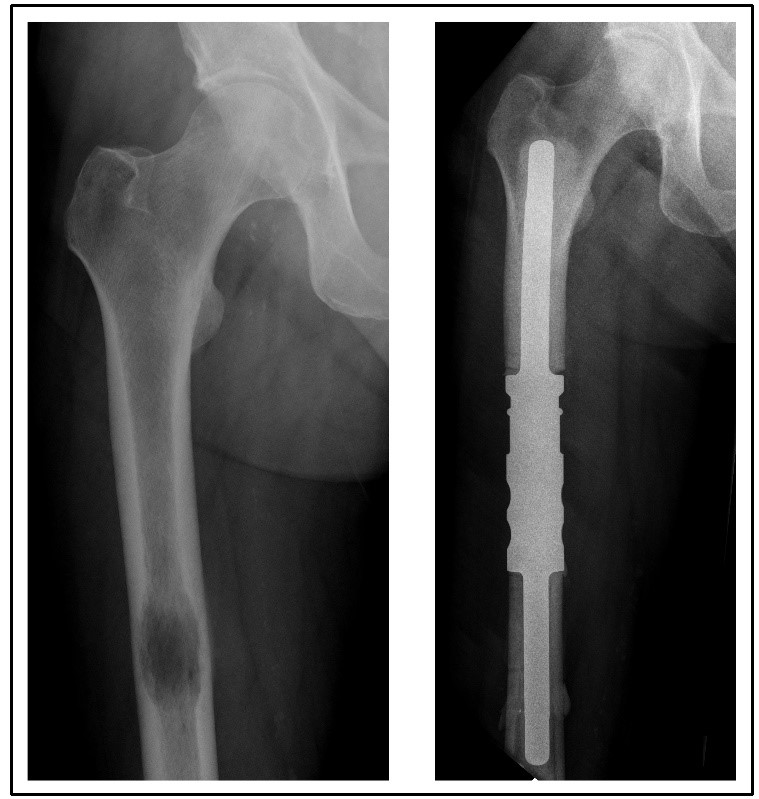

Abb.links: Metastase in einem Femur (Oberschenkelknochen), die durch Verdrängung und Zerstörung des Knochens die Stabilität gefährdet.

Abb. rechts: Nach Entfernung des betroffenen Abschnittes wurde dieser durch eine Titanprothese ersetzt.